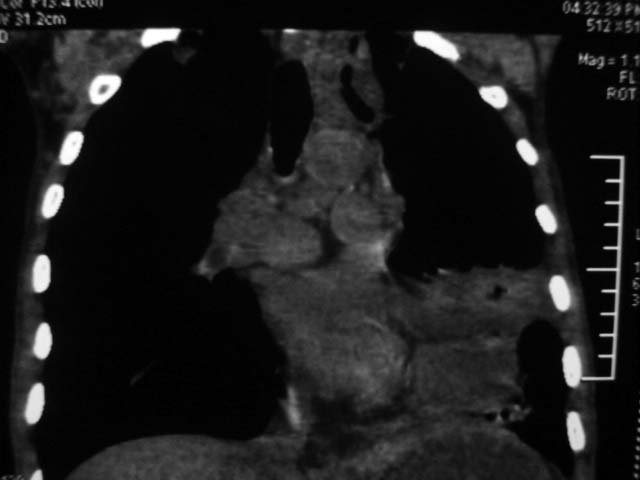

男,52岁,发热2月,糖尿病史。

抗结核治疗irpz方案,血糖未治疗,空腹15.9左右。症状无好转,左胸痛。

2、双肺见多发片状及结节状高密度影,大多数病灶中心均见“空泡征”。

3、纵隔内淋巴结肿大。

以上三点符合肺泡细胞癌的影像表现。

结果:两肺继发性肺结核并曲霉菌感染。